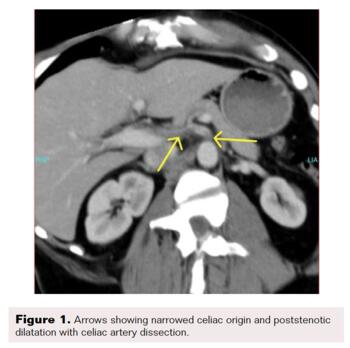

A contrast-enhanced CT scan was completed and revealed stenosis of the celiac trunk and mild bulbous dilatation of the post-stenotic celiac trunk (Figure 1). There was the appearance of a dissection flap that developed into an eccentric hypodense non-enhancing false lumen. This appeared to extend into the common hepatic arterial trunk and the splenic arterial branch, then continued to the splenic hilum (Figure 2 and Figure 3). In addition, there was a large splenic hypo-density involving almost one-third of the central spleen (Figure 4). The findings were consistent with an acute dissection of the splenic and hepatic arteries, along with splenic infarction of the central one-third of the spleen. A differential diagnosis of arcuate ligament syndrome was also considered, given the significant scoliosis seen on scout film of the CT scan (Figure 5).